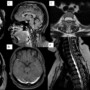

- A – Axial SWI image of brain showing hemosiderin deposits on cerebellar folia and vermis – posterior fossa superficial siderosis(arrow).

- B – T2 weighted coronal image showing collapsed bilateral peri-optic CSF sheaths(arrows).

- C – Sagittal post gadolinium T1 weighted fat saturated image showed mild pituitary congestion(arrow). Distended superior sagittal sinus may also be appreciated in the image. No brain sagging.

- D – Axial post gadolinium T1 weighted fat saturated image showing distended transverse sinuses(arrow). No abnormal meningeal enhancement/subdural collections.

- E , F and G – T2 weighted axial and sagittal images of spine showed ventral spinal longitudinal epidural collection (SLEC) with thin septations within extending from C5 to D11 vertebral levels – chronic/organized SLEC /festooned dura appearance(arrows). No discogenic spurs on screening CT of spine(image not shown).